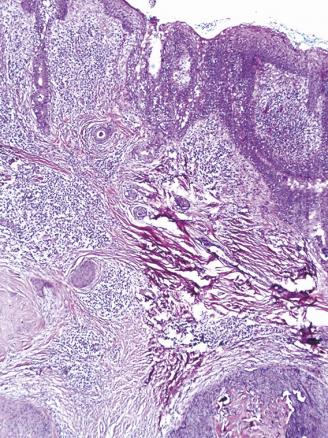

Cet homme de 40 ans, suivi pour un retard mental, consultait pour un placard papuleux blaschko-linéaire, s’étendant de la région médiocervicale à la région temporopariétale gauche évoluant depuis son bas âge, associé à de multiples nodules érythémateux suintants de la joue gauche et du cuir chevelu ainsi qu’à une lésion ulcéro-croûteuse frontale gauche (fig. 1 ). L’étude histologique montrait un hamartome sébacé et quatre tumeurs distinctes : un syringocystadénome, une tumeur combinée associant un syringocystadénome papillifère et un hidradénome, un trichoépithéliome et un carcinome basocellulaire nodulaire (fig. 2 et 3 ). L’examen ophtalmologique et l’IRM craniocérébrale étaient normaux. Le diagnostic d’un syndrome de Schimmelpenning-Feuerstein-Mims compliqué de tumeurs annexielles et d’un basocellulaire était retenu et le patient adressé en chirurgie maxillofaciale pour sa prise en charge.

L’hamartome sébacé est une malformation congénitale atteignant typiquement la tête et le cou. Il peut s’accompagner de malformations complexes dans le cadre du syndrome de Schimmelpenning- Feuerstein-Mims.1 Ce dernier correspond à l’association d’un nævus sébacé et de diverses malformations, oculaires, neurologiques notamment un retard mental. Le développement classique de tumeurs bénignes sur nævus sébacé est rapporté dans la littérature alors que les tumeurs malignes sont plus rares, dominées par le carcinome basocellulaire.2 Le traitement de choix est la chirurgie. Des alternatives peuvent être proposées, notamment la dermabrasion, le laser CO2 et la photothérapie dynamique.